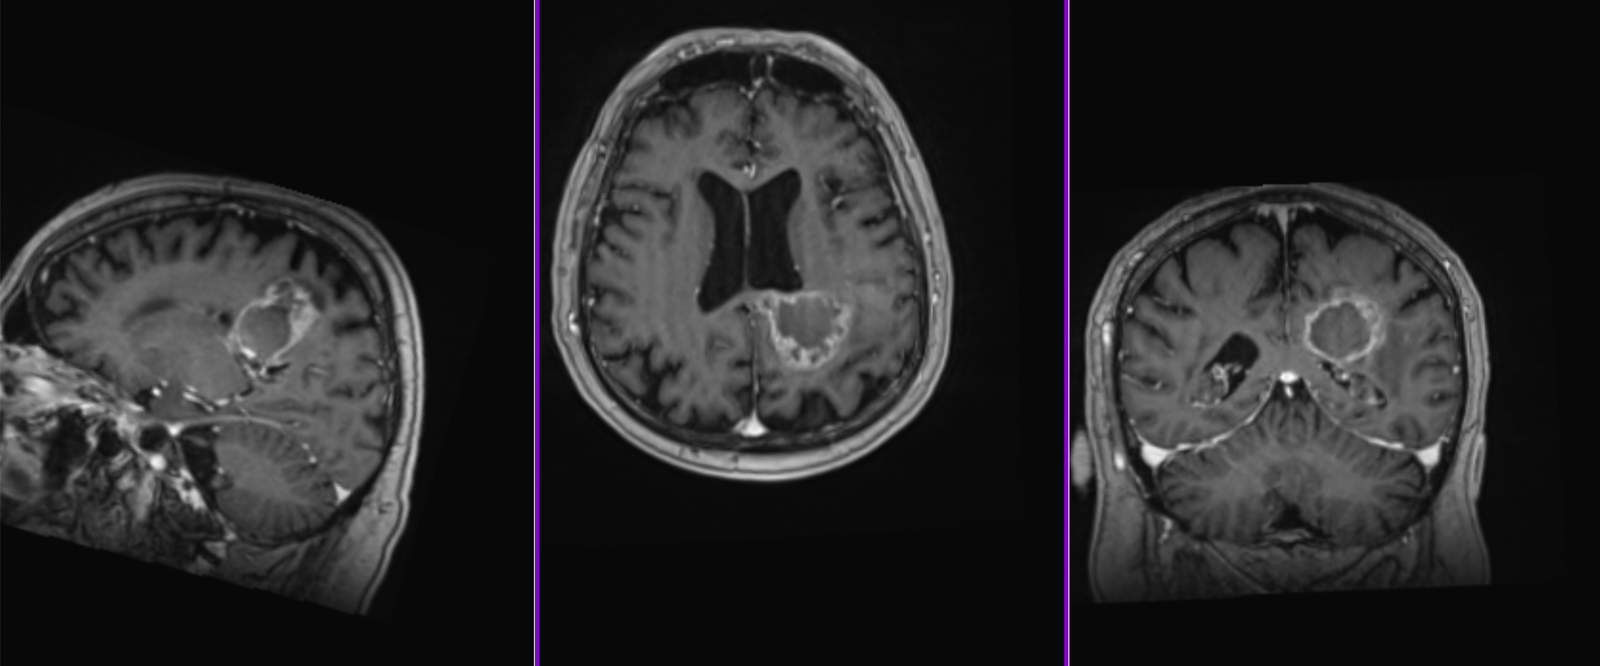

La nivel imagistic, glioblastomul apare adesea ca o leziune relativ bine delimitată, cu captare inelară de contrast și necroză centrală. Pentru ochiul neavizat, aceasta poate sugera o tumoră care ar putea fi „scoasă complet”. În realitate, ceea ce vedem pe RMN reprezintă doar componenta cea mai densă tumoral.

Imagistica – instrument esențial, dar imperfect

RMN-ul cerebral este standardul diagnostic, dar trebuie interpretat în context.

Pe lângă secvențele convenționale, tehnicile avansate aduc informații suplimentare:

- perfuzia evidențiază angiogeneza tumorală

- spectroscopia reflectă metabolismul celular

- DTI (tractografia) arată relația cu tracturile din substanța albă

Cu toate acestea, niciuna dintre aceste metode nu poate delimita complet infiltrarea microscopică. De aceea, planificarea chirurgicală și terapeutică trebuie să țină cont de această limitare.

Recidiva – inevitabilitate biologică

Recidiva nu este o eventualitate, ci o etapă a evoluției bolii.

Aceasta apare de obicei:

- în vecinătatea cavității de rezecție

- rar, la distanță

Etapa 3 – Controlul RMN (cu contrast)

- Primul RMN postoperator – la 24 ore de la operație.

- Al doilea RMN – la 3 săptămâni de la operație (va fi folosit și pentru planul de radioterapie).

- Al treilea RMN – la 6 săptămâni de la încheierea radioterapiei.

- Următoarele RMN – la interval de 2 luni.